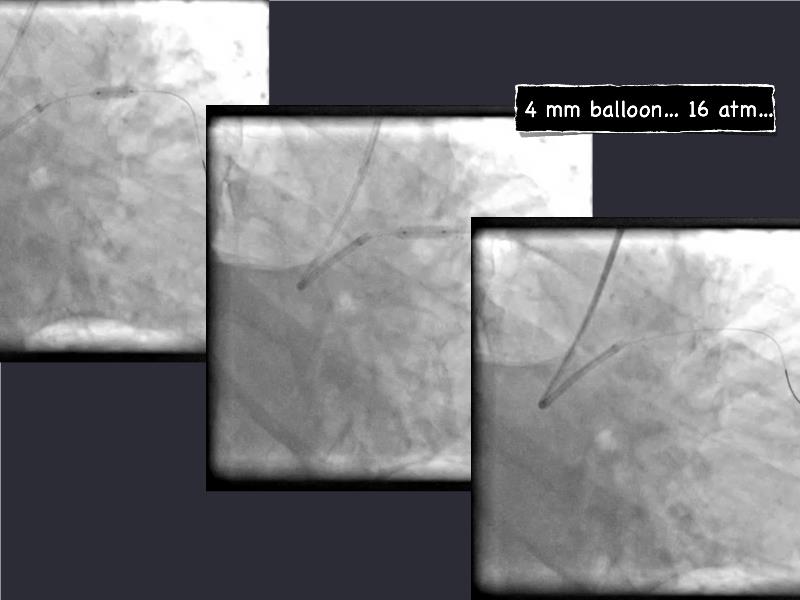

- To understand novel tools and techniques for effective management of bifurcation lesions and long diffused lesions using dedicated stenting solutions